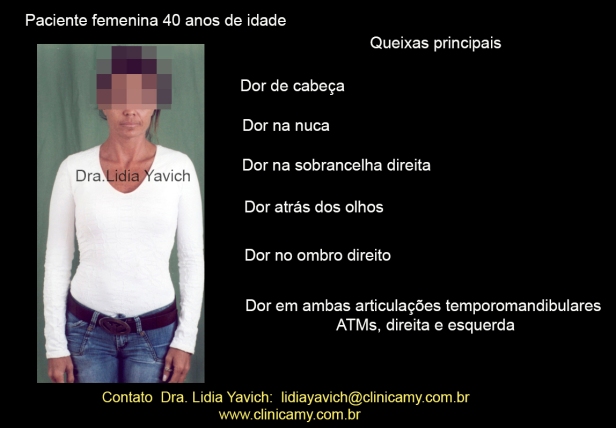

Paciente de sexo feminino, 40 anos de idade se apresenta na consulta encaminhada pelo seu médico reumatologista COM MUITA DOR NAS ATMs (articulações temporomandibulares) PONTADAS NA CABEÇA E LIMITAÇÃO DA ABERTURA BUCAL.

A paciente refere estalos na ATM direita, dificuldade para abrir a boca, dificuldade e dor na mastigação. Relata ter bruxismo.

Relata sentir dor de cabeça, dor na nuca, dor na sobrancelha direita, dor atrás dos olhos, dor no ombro direito. Dor em ambas as articulações temporomandibulares, sendo mais forte na direita.

A paciente assinala na ficha os pontos de dor mais importantes.